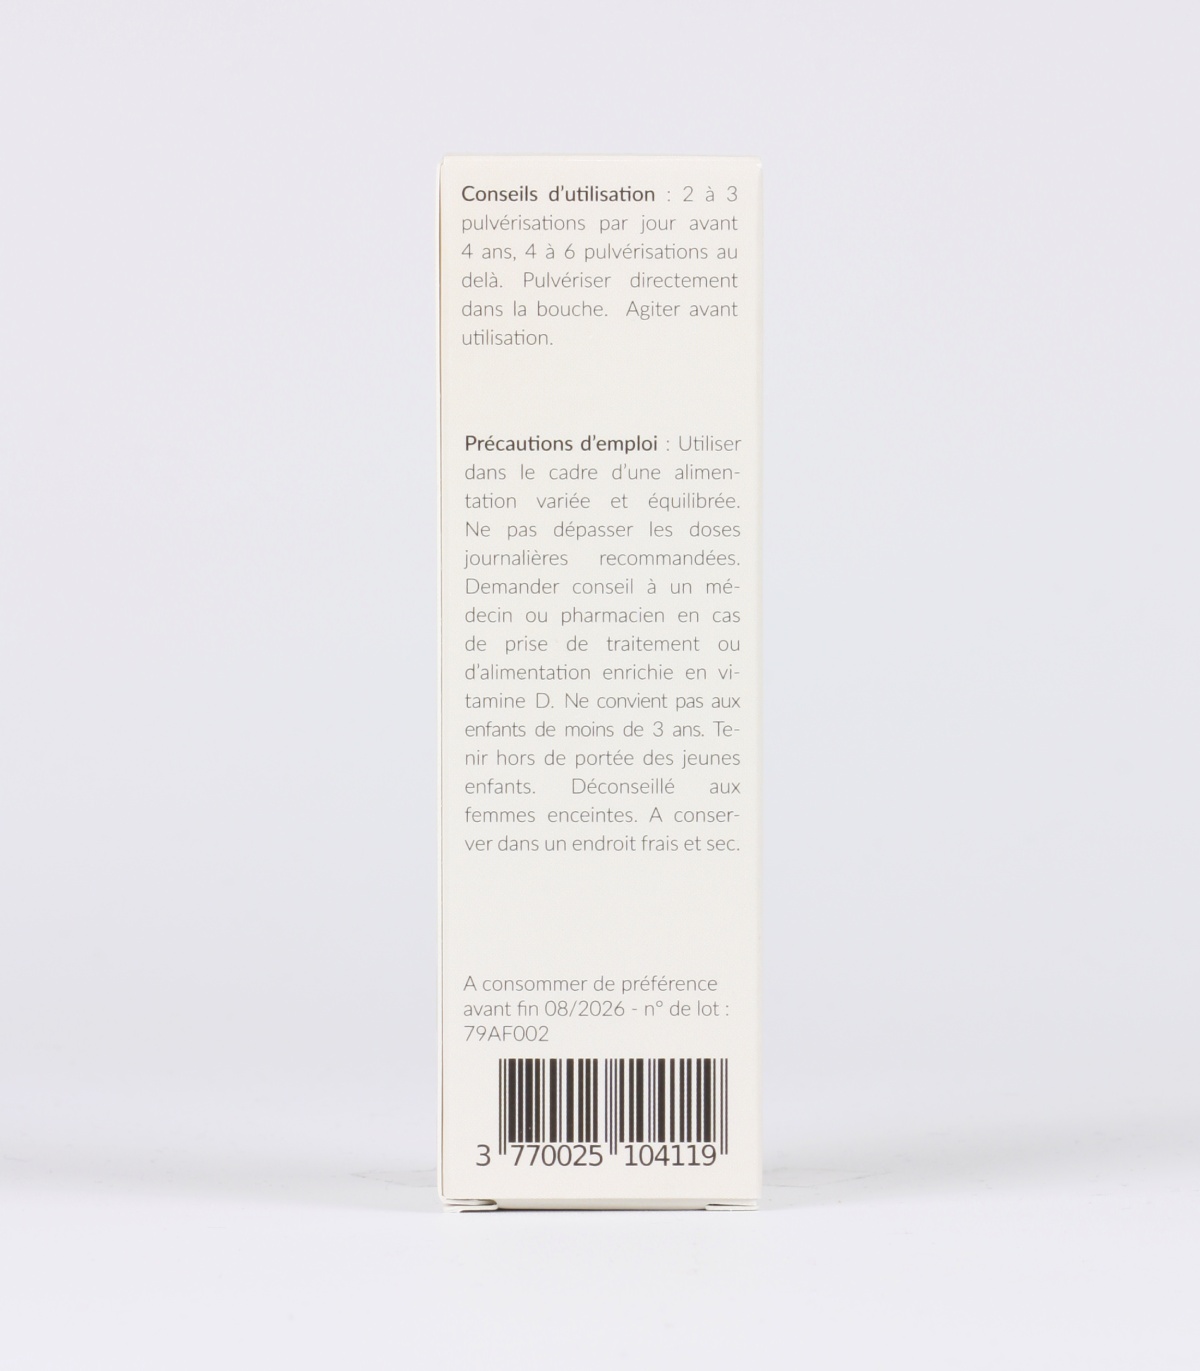

CONSEILS D’UTILISATION :

2 à 4 gélules de Calcium Complexe par jour, à consommer au moment des repas idéalement. Répartir si possible en deux prises : une le matin et l’autre le soir.

Nous recommandons de consommer Calcium Complexe en continu ou à minima durant 3 mois. Adaptez les doses à chaque situation, au degré de carence identifié ou au niveau de risque.

Calcium complexe est tout à fait recommandé aux femmes enceintes et allaitantes. Les recommandations officielles n’imposent pas d’augmentation des apports calciques pendant la grossesse ou l’allaitement, mais la vigilance sur la qualité des sources reste essentielle.

QUELLES SONT LES PRECAUTIONS D’UTILISATION D’UN COMPLEMENT A BASE DE CALCIUM ET DE VITAMINE K2?

En cas d’hypercalcémie, hypercalciurie, lithiase rénale calcique, informez impérativement un professionnel de santé avant toute prise.

Déconseillé aux personnes sous anti-coagulants. Contrindiqué en cas de traitement anti-vitamine K.

Les compléments alimentaires doivent être utilisés dans le cadre d’un mode de vie sain et ne pas être utilisés comme substituts d’un régime alimentaire varié et équilibré. Ne pas dépasser la dose journalière recommandée sans avis médical. Tenir hors de portée des enfants. Conserver le produit à l’abri de l’humidité, de la chaleur et de la lumière.